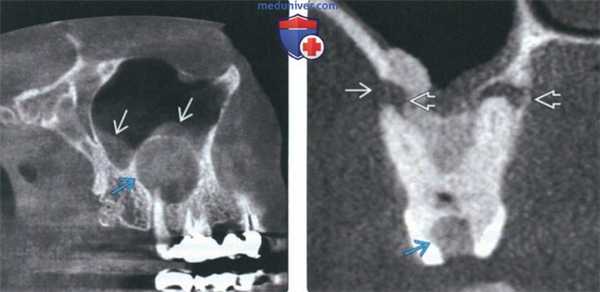

(Слева) На сагиттальной КЛКТ визуализируется крупная радикулярная киста, смещающая дно верхнечелюстной пазухи кверху и занимающая ее нижнюю треть. Обратите внимание на воспалительные изменения пазухи.

(Справа) На профильном срезе (КЛКТ) визуализируется крупная кариозная полостьв нежизнеспособном моляре; также видны два периапикальных абсцесса. Поражение щечного корня приводит к деструкции щечной кортикальной пластинки альвеолярного отростка. Сужение пульповых каналов необходимо отметить как вероятное осложнение эндодонтическою лечения.

(Слева) На панорамной рентгенограмме определяются множественные просветления в области вершин корней зубов. Вершины первых моляров закрыты; апикальные просветления обусловлены рарефицирующим остеитом. Вершины корней второго моляра и второго премоляра еще формируются.

(Справа) На периапикаль ной рентгенограмме определяется разрежение вокруг верхушечной трети корня временного центрального резца справа, на ко торое накладывается фолликул постоянногозуба-преемника.